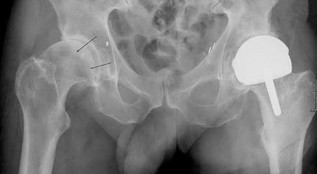

A 32-year-old male is brought to the trauma bay in hemorrhagic shock after a motorcycle crash. An anteroposterior radiograph of the pelvis demonstrates an APC-III injury. A pelvic binder is applied. To maximize reduction of the pelvic volume, at what anatomical landmark should the binder be centered?

Explanation:

Pelvic binders should be centered over the greater trochanters to effectively close the pelvic ring and reduce pelvic volume. Placement over the iliac crests or ASIS can paradoxically widen the true pelvis or fail to achieve adequate reduction in an open-book pelvic injury.